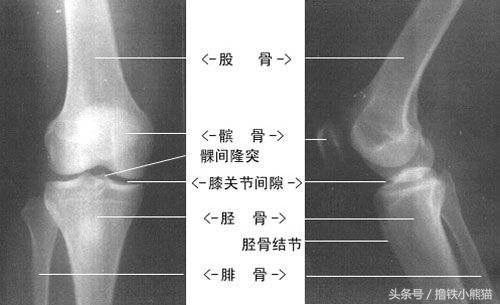

识别方法:我们的膝盖前部通常出现疼痛,但是在髌股关节退行性病变的情况下(在年龄较大的人中更常见),这种疼痛可能放射到膝盖后部。局部压痛可能出现在髌骨的任何部位,前内侧关节线压痛很常见,应该评估髌股关节的轨迹。韧带测试有助于排除前十字韧带损伤。体检应包括对下肢对齐和同侧髋关节的总体评估。X线片可能会显示出髌股关节不对齐、骨发育障碍和退行性病变。

识别方法:运动员反映最多的是在活动之后出现局部疼痛和轻微肿胀。任何旋转腿部动作或极端的运动往往都会加剧疼痛。运动员睡觉时可能会感到膝盖位置疼痛。几乎所有导致膝关节疼痛的损伤都会引起下楼梯疼痛或不舒服。转动法有助于诊断半月板撕裂,比如在向外和向内旋转腿部的同时弯曲和伸展膝关节,如果这些动作能够重现疼痛或症状,表明可能发生了半月板撕裂。在转动膝关节时如果听到咔嗒声,可能意味着半月板在活动。